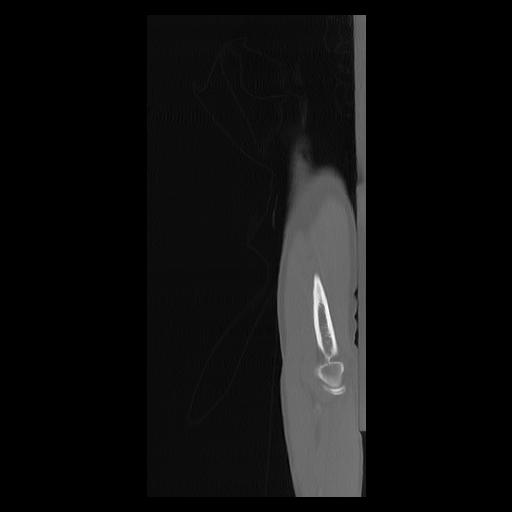

33 PULMON,CE,Sagittal,3.000,PULMON,Sagittal,